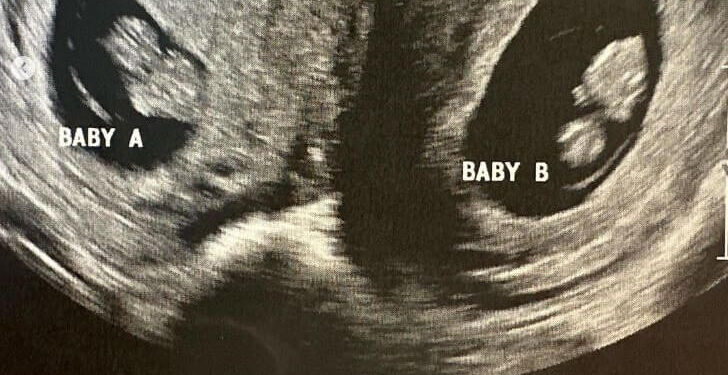

მაისში, ორსულობის მერვე კვირაზე, ულტრაბგერაზე ვიზიტისას, სამი შვილის დედამ შეიტყო, რომ ის არა მხოლოდ ტყუპებს ელოდებოდა, არამედ უფრო მეტიც — ნაყოფი ორივე საშვილოსნოში იყო წარმოდგენილი.